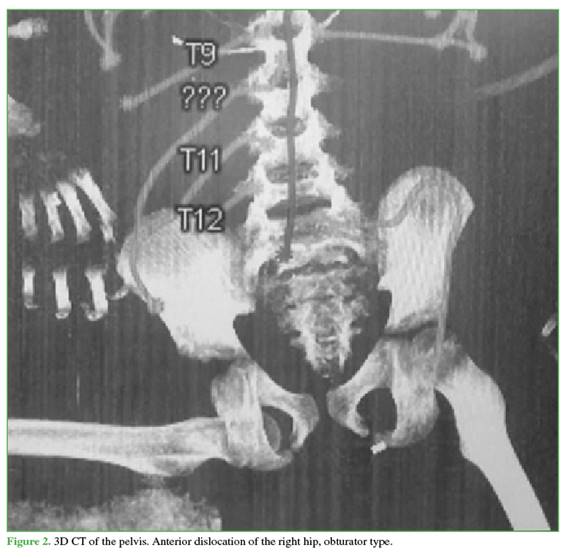

Orotracheal intubation was performed. A cranial CT scan showed an epidural hematoma and a frontotemporal fracture without surgical indication. Initial pelvic CT revealed right hip joint incongruity consistent with an anterior dislocation of obturator type (Figure 2); associated injuries were ruled out.

After stabilization, closed reduction under sedation was performed 8 hours after the accident. With the child in the supine position and the knee flexed at 90°, longitudinal traction was applied; simultaneously, the proximal femur was displaced laterally using a strap and external rotation, achieving successful clinical reduction. Stability maneuvers were positive, and reduction was confirmed by fluoroscopy (Figure 3).